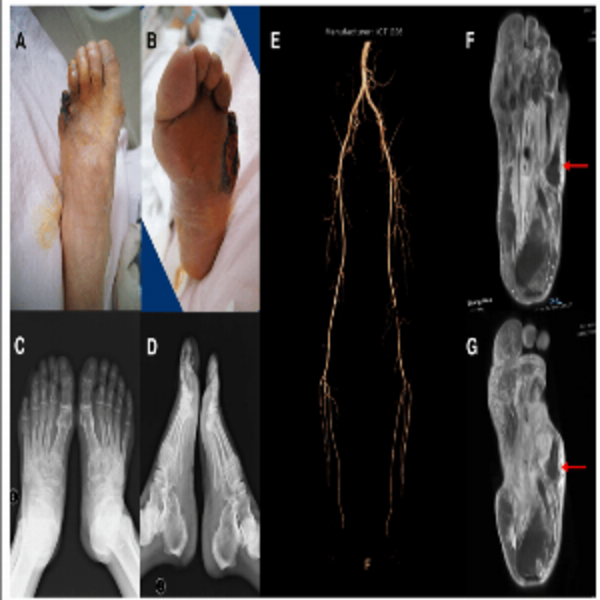

We Provide Best Doctor For Ankle Replacement Surge...